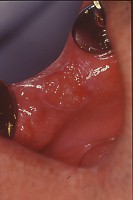

頬粘膜癌 (carcinoma of the buccal membrane)

好発部位は大臼歯部に対する頬粘膜面で、なかでも臼後部のものが悪性度が強い。

症例1